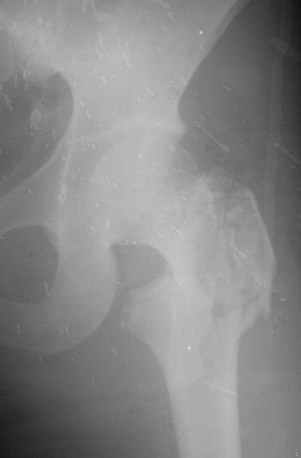

Уважаемые коллеги! На консультации обратились родственники больной, получившей в автопроисшествии неделю назад вот такой закрытый перелом.

Что делать?Пациентке 25 лет.

Такой перелом типичен для пожилых, и тут лучший выбор - гамма-подобный гвоздь. То есть мощный фиксатор в шейку (11-12 мм) и 15-17 мм гвоздь.

Тут, с учетом молодого возраста, в порядке предпочтения у нас были бы реконструкционный гвоздь (он потоньше, 13 мм, и винты в шейку 6,5 мм), гамма/проксимальный гвоздь, динамический бедренный винт, клинковая пластина, аппарат (пучок спиц в шейку и два стержня в диафиз), скелетное вытяжение.

Перелом вроде был вертельный? Или показали не все снимки? Некроз головки при вертельных и подвертельных переломах - казуистика.

Снимок единственный. Все, что мне показали на консультации я представил.

Снимок не очень, да и аксиального для такого решения не хвает, конечно. Но мне кажется, что перелом не только чрезвертельный, но и вплоть до субкапитального.

Больная одна и таже. Ей 25 лет. При анализе попытки операции исхожу из местных условий - широкий доступ, без ЭОПа, несколько попыток провести направляющую спицу, а потом винты - реальная, на мой взгляд, перспектива некроза головки в послеоперационном периоде.

ЮАБ> конечно. Но мне кажется, что перелом не только чрезвертельный,

ЮАБ> но и вплоть до субкапитального.

Не заметил на показанном снимке шеечного перелома. По возможности поглядеть бы на снимки в динамике и/или другие проекции. Но если Вы уверенно отмечаете перелом шейки бедра - отказ от оперативного лечения у молодой больной вряд ли обоснован.

ЮАБ> исхожу из местных условий - широкий доступ, без ЭОПа,

Зачем широкий доступ? Репозиция делается либо на тракционном столе, либо дистрактором, любой из обсуждавшихся фиксаторов вводится зактрыто, доступ только для обнажения ската вертела и чуть дистальнее, если речь о пластинке. Достаточно рентгеновских снимков в операционной.

ЮАБ> несколько попыток провести направляющую спицу, а потом

ЮАБ> винты -

На первом же снимке надо уже разместить ориентиры, в частности, спицу через мягкие ткани по передней поверхности шейки, ввести 1-2 две спицы в шейку. О каких винтах говорите - не пойму. Винтами тут синтезировать как при переломе шейке нельзя из-за разрушения вертельной области, тут нужна железка с угловой стабильностью - гвоздь, DHS или клинок. На худой конец трехлопастной гвоздь с диафизарной накладкой.

Некроз головки - это, в первую очередь, следствие перелома шейки. Которого, может, все-таки нет.

ЮАБ> Что касается консервативного лечения, то при таком вальгусе и

Типичным для неправильного сращения перелома проксимального отдела бедра является варус. О каком "таком вальгусе" идет речь - непонятно.

На едиственном снимке никакого вальгуса нет, видна только наружная ротация периферического отломка, что характерно для первичного снимка. После укладки на шину с отведением и вытяжения по оси положение отломков улучшится. Вот тут бы контроль и сделать.